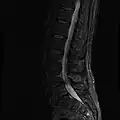

MRI

MRI lumbar spine with degeneration (sagittal T2 FRFSE) -

MRI lumbar spine with degeneration (sagittal T1 FSE) -